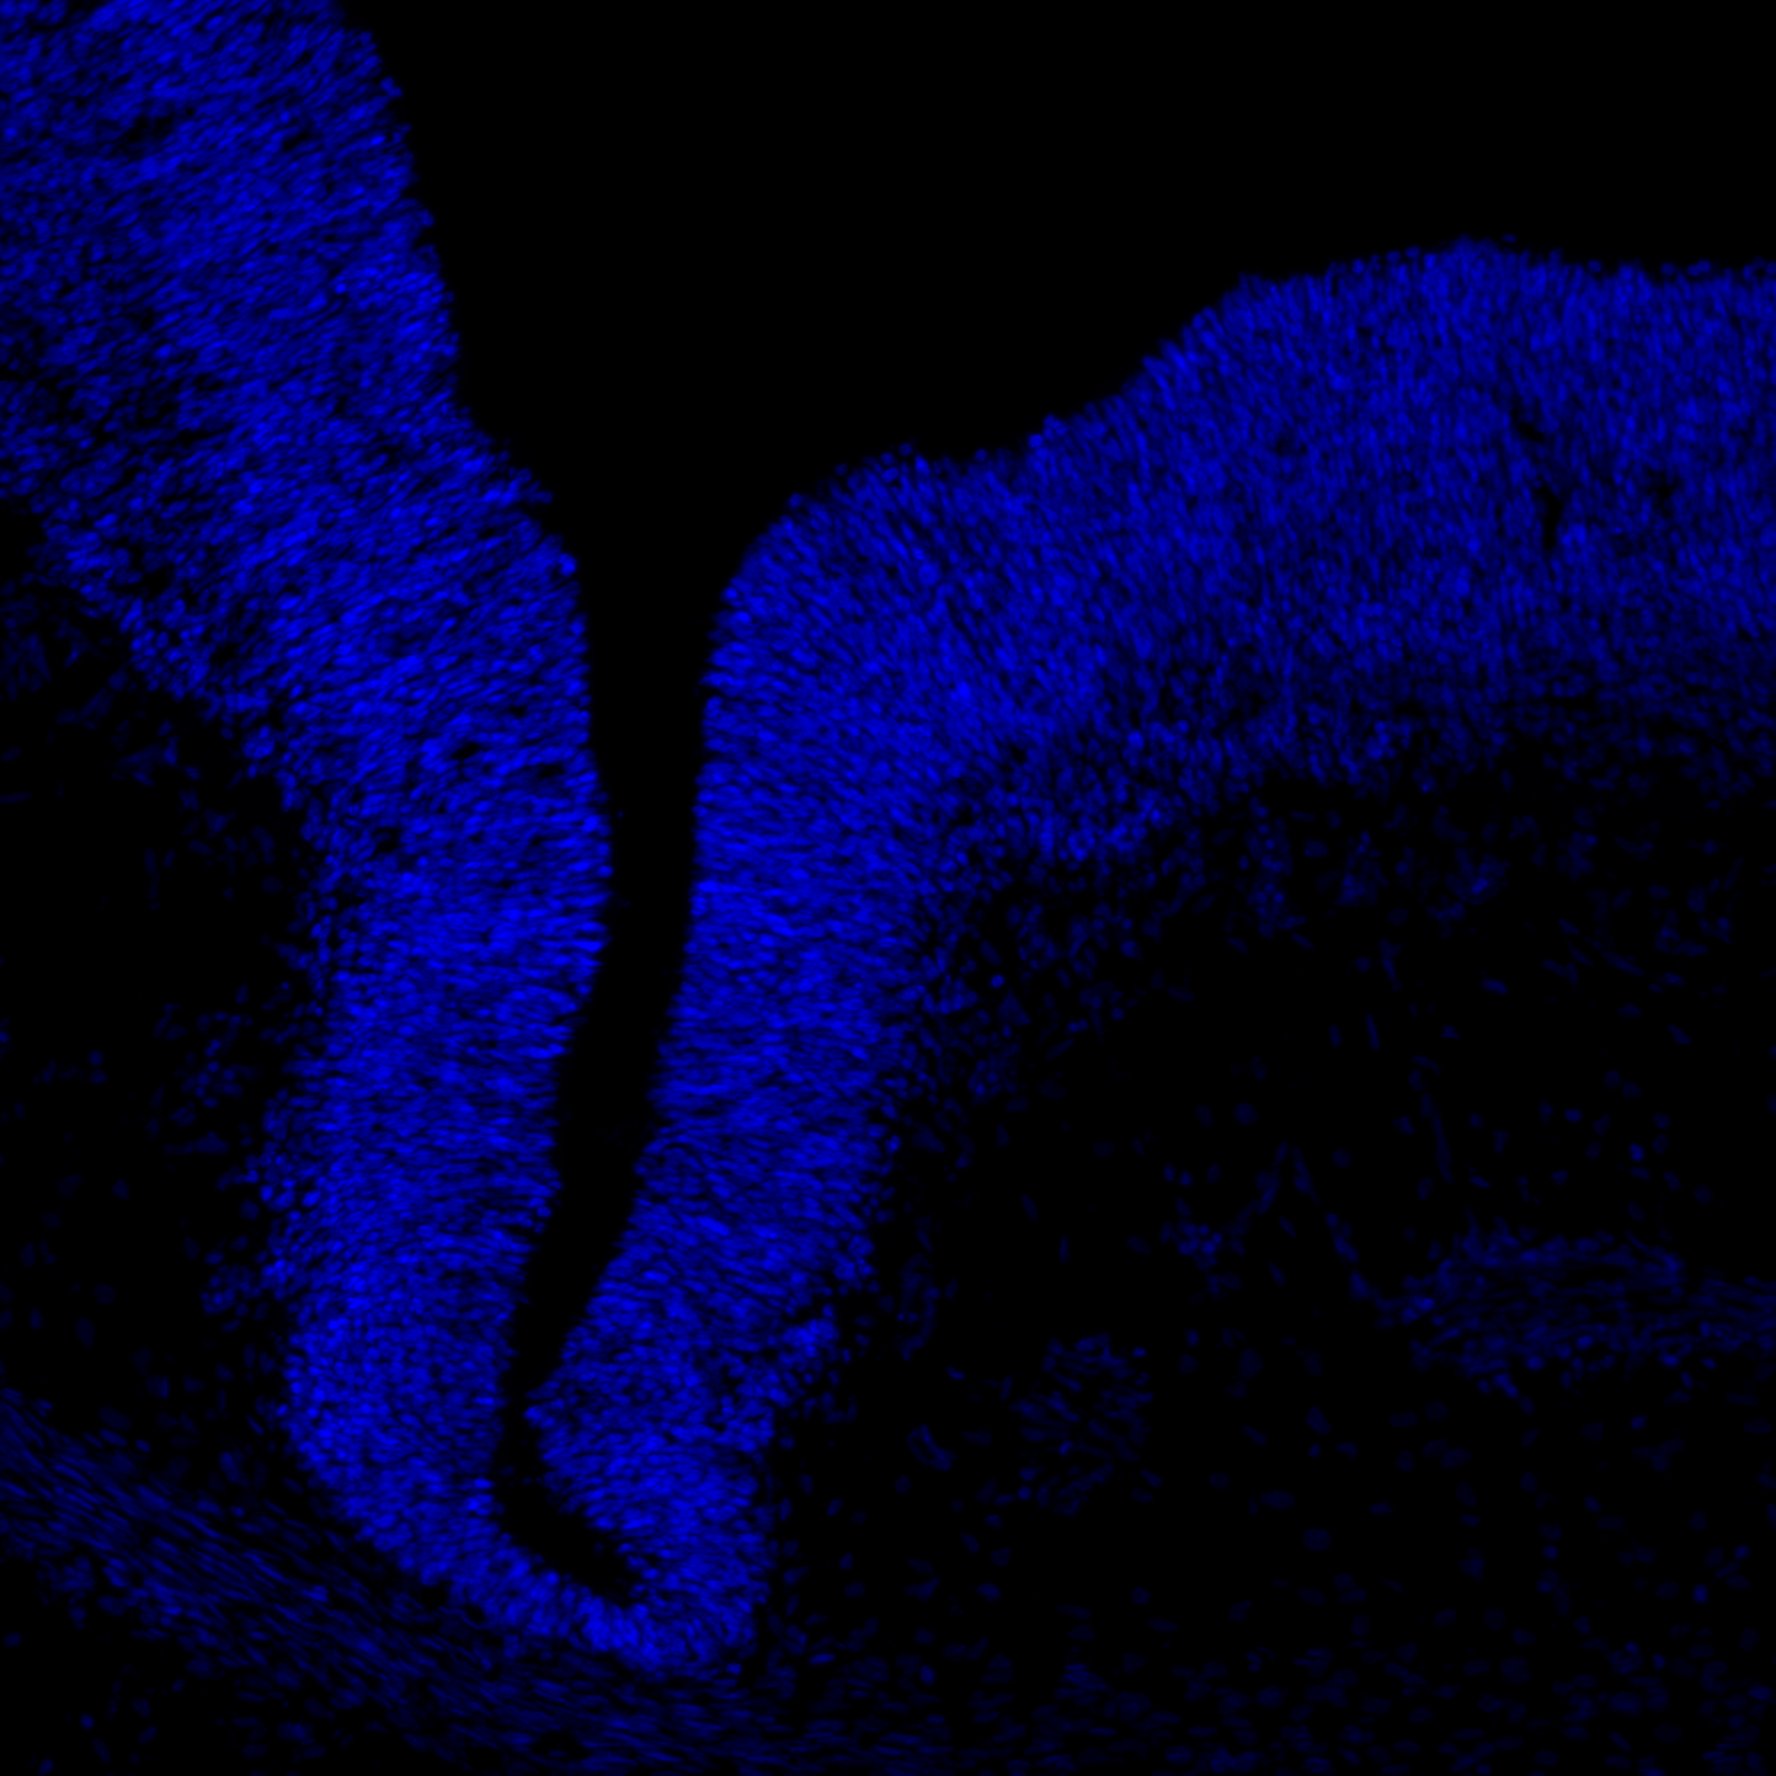

DAPI

6PCW human midbrain